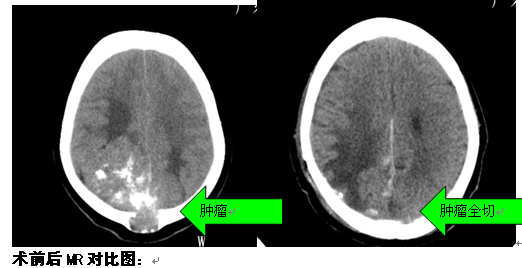

陈女士,28岁,于2年前无明显诱因出现头痛,偶有呕吐;半年前因出现动作迟缓、行走不稳;上述症状呈进行性加重,当地医院行头颅CT平扫提示双侧枕顶巨大肿瘤,今为进一步诊治来我院就诊。诊断:双侧枕顶部镰窦旁巨大脑膜瘤

治疗:入院后予完善相关检查,先行“肿瘤供血血管介入栓塞术”,术后在全麻下行右枕顶部占位性病变切除术,最后全切肿瘤。术中出血约1400ml,输血约1000ml。经治疗,患者目前无头晕、头痛,无恶心、呕吐等不适,肌张力正常,右下肢肌力3级,生理反射存在,病理征阴性。